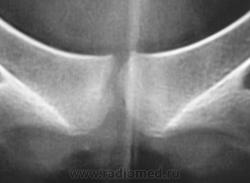

2. Лонное сочленение очевидно,подверглось значительному растяжению (имеется локальный вакуум-феномен слева), умеренно выраженые явления симфизита (опять же - постравматического).

Посттравматический симфизит - это такой медицинский диагноз есть? Тогда уж лучше - симфизопатияУлыбаюсь.  По поперечному перелому Л5 - тангенциальный эффект, сложение теней. По хорошему, надо бы доснять поясничный отдел позвоночника, в том числе в косых проекциях - на дугоотростчатые суставы, и грудо-поясничный переход.

1. спорить по поводу симфизита (симфизопатии) не буду - хрен редьки не слаще.

1. По первым снимкам не отпускало впечатление о повреждении левого крестцово-подвздошного сочленения. После подготовки вроде-бы все нормально, но все равно что-то гложет.

Поздно заметил ветку.. увидел симфизит, перелом остистого L4, мазоль Co 5, и  конечно spina bifida S1 ))) глянуть бы межпозвоночные..